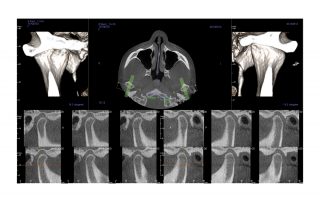

i-CAT FLX V17

Designed to accommodate the widest range of clinical applications, the V17 is the most flexible of the V-Series options. This unit has a maximum and scalable FOV of up to 23 cm x 17 cm. The V17 is used most often by orthodontists, oral maxillofacial surgeons and oral radiologists.